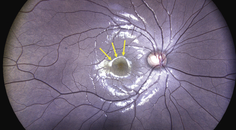

OCT is also valuable in identifying AMD at early stages. Drusen, a hallmark of AMD, are identified on OCT as discrete elevations of the retinal pigment epithelium (RPE) layer at the level of Bruch membrane (Figure). Drusen that form above the RPE are known as reticular pseudodrusen and are a more ominous sign. Patients with this type of drusen are much more likely to progress to advanced disease.11

Figure. OCT findings show numerous medium-sized drusen (>63 μm to ≤125 μm) in a patient with early AMD. No pigmentary abnormalities are present.